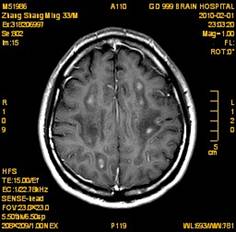

案例2 患者,女,30岁,二氯乙烷中毒性脑病的头颅MR。表现为双侧大脑半球皮层下白质、双侧外囊、双侧苍白球及双侧小脑齿状核内广泛片状、斑片状长T1长T2异常信号影,FLAIR序列呈高信号,增强后病变未见明显强化。

给予抗炎、脱水、疏通血管及营养神经等药物治疗。经过40天的对症治疗,痊愈出院。